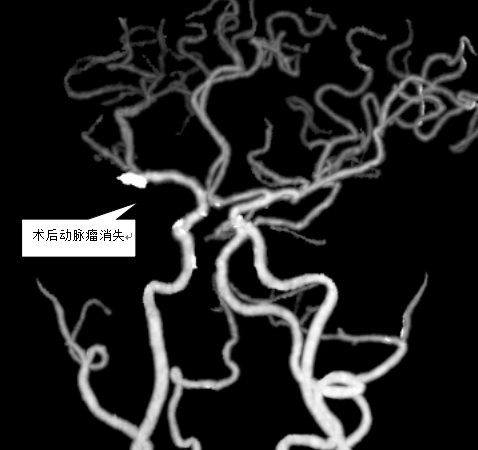

凸出位置为动脉瘤